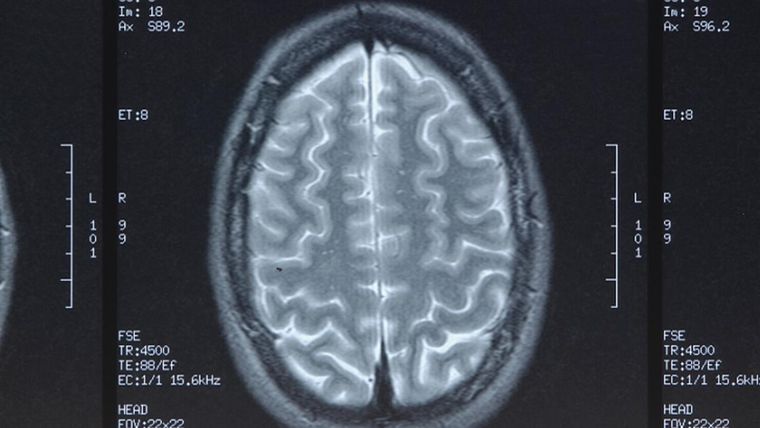

En un principio, el hombre, llamado Xiao Chen, pensaba que sus dolores se debían a las pocas horas de sueño, pero con el pasar de los años desestimó esa posibilidad y decidió ir a un hospital. El caso asombró a los profesionales quienes le realizaron una resonancia magnética.

En el estudio hallaron un objeto extraño que se encontraba alojado en el lado izquierdo de la cabeza, y luego de una inspección se reveló que el objeto era una bala.